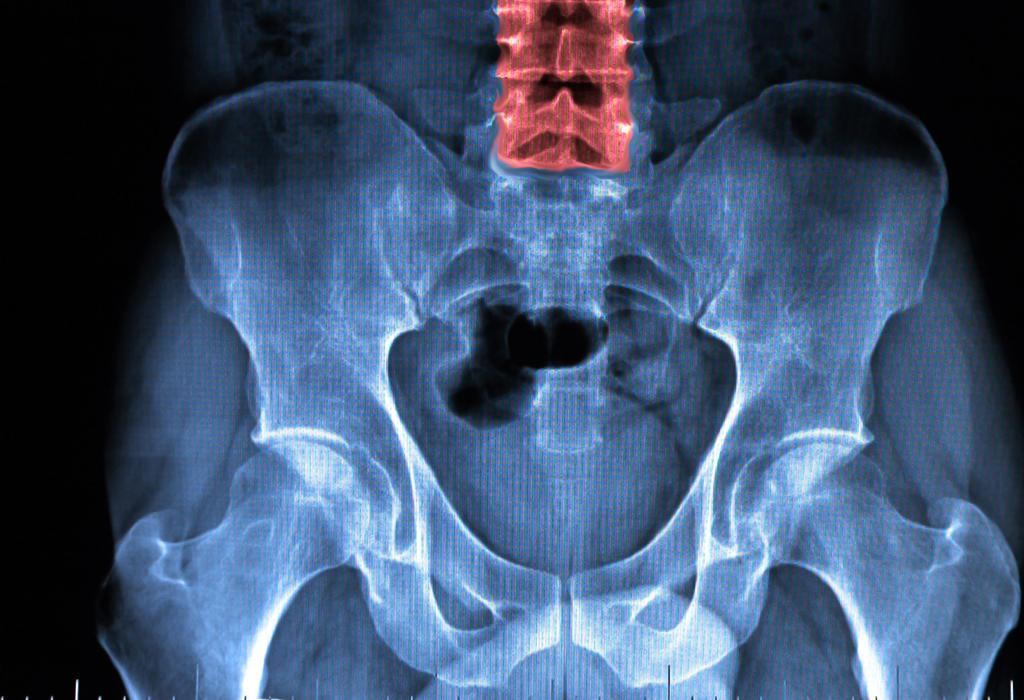

Tim je zabilježio 100 prijeloma kuka tijekom praćenja. Među sudionicima, oni koji su konzumirali više vitamina C – bilo kroz hranu ili suplemente – smanjili su rizik od puknuća kuka. Pripadnici ove skupine imali su 44 posto manje vjerojatnosti da će imati prijelom kuka od onih s manjim unosom vitamina.

Prijelomi kuka su čak opasni po život. Ljudi postaju slabi i hospitalizirani. To također može rezultirati trajnim invaliditetom. Povećani unos vitamina C jednostavan je način da se spriječi.